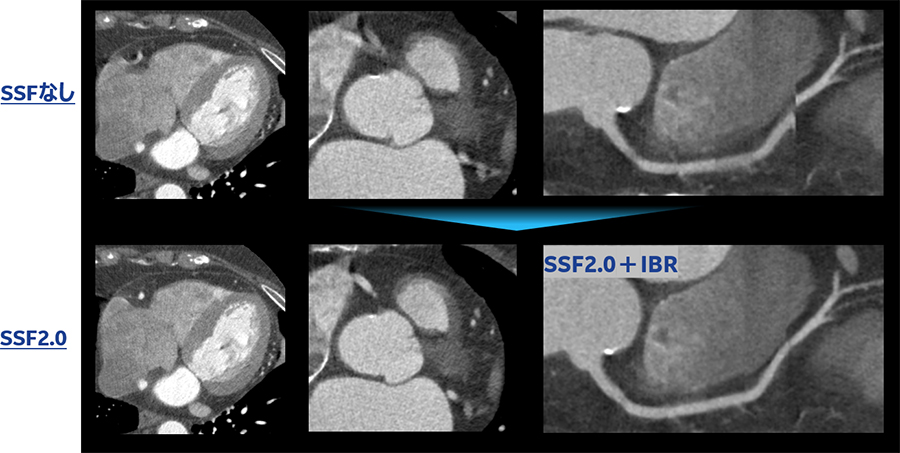

74歳 女性 狭心症疑い βブロッカーあり ミオコール使用 撮影時心拍数70

rotation time 0.35s/rot pitch 0.24 心位相45%

Asend_YokohamaSougou_11.jpg